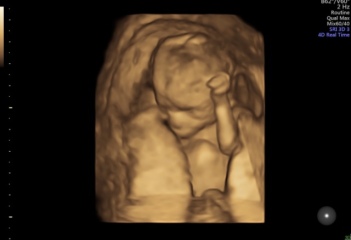

@Cassarat @xalexandra

we found out this morning that it’s… a… GIRL! Soooooo happy can’t believe it still

@Sprinklerainbows omg!!! Congratulations 💕💕💕💕 that's amazing news and love them scan pics, such good ones! She looks like she's doing ok in there 🥰

Sprinklerainbows · 10/12/2022 14:31

@xalexandra ahhh thank you. One of each is the dream for us.

they did a health check and apparently all looks well in there, another anterior placenta (I KNEW IT)

they took a long time deciding the gender so hope it’s right 🤣